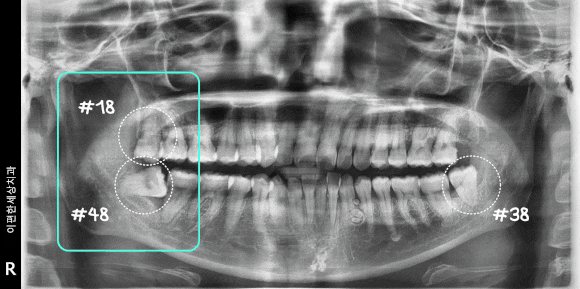

촬영일 : 240610

불편함을 느끼고 계신 오른쪽을 살펴보니

48번의 경우 옆으로 누워 부분 매복 되어 있는 까다로운 상태였습니다.